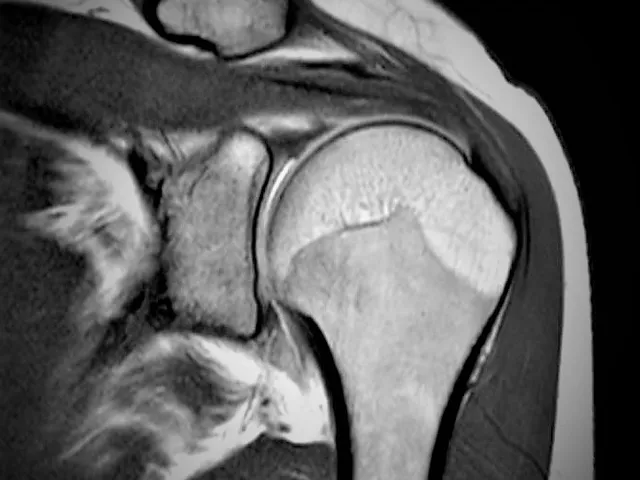

This module MRI of the shoulder – rotator cuff I provides steps for a structured approach for reporting the shoulder but with a focus on the rotator cuff. The rotator cuff is a challenging structure to assess with its complex and obliquely orientated anatomy.

In this module you will find different examples of rotator cuff tears and learn how to describe them, based on the recent and commonly agreed radiological literature.

While you go through the cases with the organized template you will become familiar and feel more confident with every next MRI of the shoulder. Several answers provide additional information on the how and why of the answers.

For your training several cases have been choses that may show limitations e.g. motion artefacts or suboptimal imaging planes as this is frequently the case in your clinical practice. Patients are in pain, or too large for regular positioning which brings on extra challenges to assess the relevant pathology. No perfect images from textbooks but daily practice defiances. We hope you’ll be able to deviate the challenge and learn going through the images